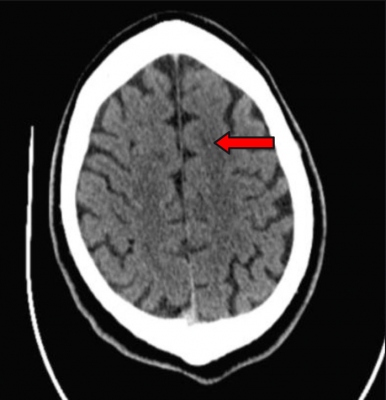

Obr. 1 – Geometrický průměr (n = 6) – Pradaxa 200 mg. aPtt – aktivovaný parciální tromboplastinový čas; ECT – ekarinový koagulační čas; INR – mezinárodní normalizovaný poměr; TT – trombinový čas.Zároveň však bylo jasné, že nejde o selhání léčby jako takové. Bezprostředně provedené tomografické vyšetření (CT) prokazovalo nevýrazné hypodenzity v levé frontální oblasti parasagitálně a okluzi periferie levé arteria cerebri anterior (ACA) (obr. 2).

Obr. 2 – CTAG s průkazem okluze periferie ACA vlevo• Časová osa: